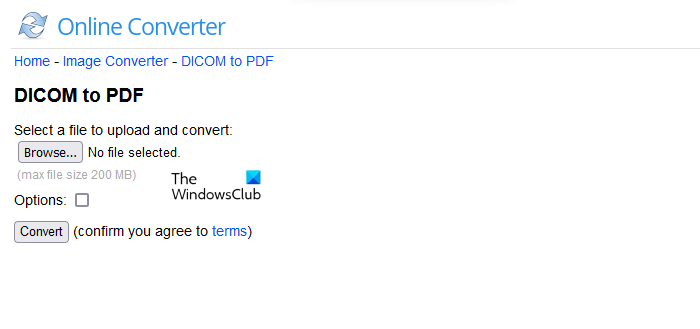

5] Online Converter

Online Converter is a simple online tool that lets you convert DICOM images to PDF files. It is a free tool that offers a maximum size of 200 MB to upload a file. To use this tool, visit onlineconverter.com. Now, click on the Browse button and upload a DICOM image file. You can resize the DICOM image file before converting it into PDF format. To do so, click on the Options checkbox and then enter the desired dimensions. When you are done, click on the Convert button. After converting the image, you can download it to your system.

The uploaded file will be deleted automatically from its server after 24 hours or you can manually delete it by clicking on the Delete button. If you click on the Send to phone link, you will see a QR code. Scan that code using a QR code scanner on your smartphone if you want to download the converted file on your phone.